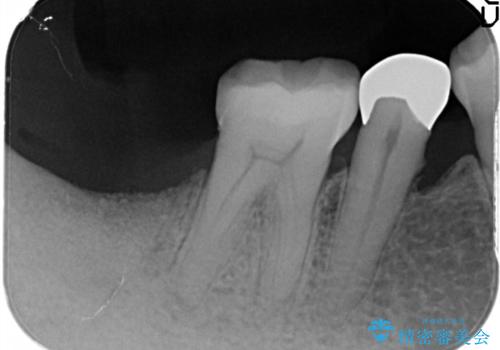

重度の歯周病により保存困難と診断し、抜歯後にインプラント治療を行いました。

抜歯後十分な骨の回復が認められず、単独の骨増生を行った後にインプラントを埋入しました。

インプラント埋入時に骨が足りない場合にはインプラント埋入前に骨増生を行います。また、インプラント周囲の角化歯肉が不足した場合は角化歯肉の移植も行うことがあります。